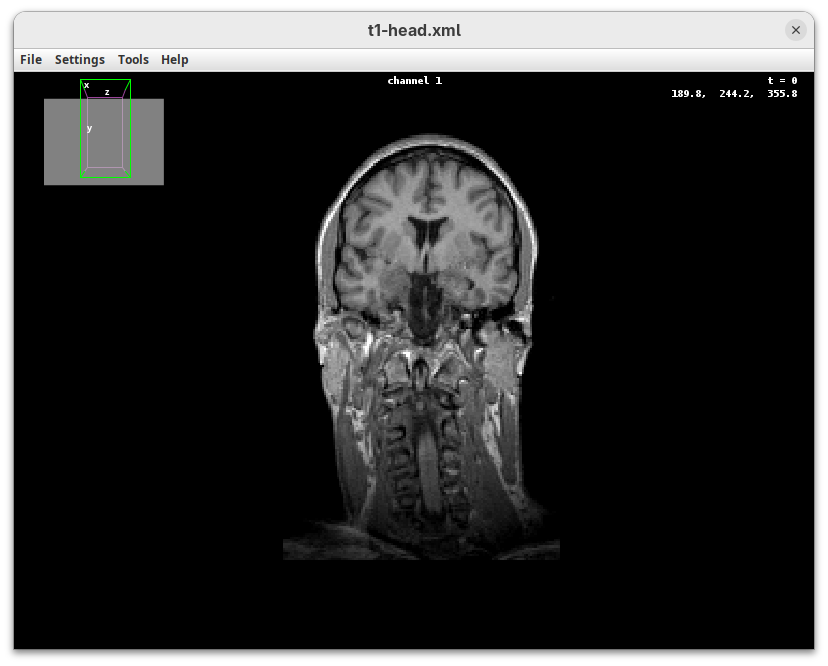

BigDataViewer (Pietzsch et al. 2015) is one of the most important tools for visualizing large, multidimensional datasets. It provides a simple and intuitive interface and shortcuts to swiftly navigate through your sample even on a regular laptop. This is possible because of the underlying file format used by BigDataViewer: the XML/HDF5 combo. Therefore, before opening the plugin, we must convert our dataset.

The BigDataViewer interface will open showing an optical section of the head sample.

Getting familiar with BigDataViewer is an essential skill for navigating large 3D datasets. It’ll also be important for the multiview registration pipeline. So, take the time to learn the basic commands and shortcuts. It is nicely intuitive. The BigDataViewer’s page on the ImageJ Docs has the official documentation and we can also go to Help > Show Help for an up-to-date overview.

Some of the movements to try:

Left-click and drag: turn the sample around the mouse pointer at any arbitrary angle.Right-click and drag: move the sample in the XY plane (of the view).Scroll: move through the Z plane (of the view). UseShift+Scrollto move fast.Ctrl+Shift+Scroll: zoom in or out.

But, most importantly, are the commands to put your sample back to its original orientation or along any of the original dimension axes:

Shift+Z: orient the sample on the XY plane.Shift+X: orient the sample on the ZY plane.Shift+Y: orient the sample on the ZX plane.

Finally, a visual tip. The default interpolation between image slices is nearest-neighbors. Press I to activate the tri-linear interpolation to obtain a much smoother (and improved) data visualization.